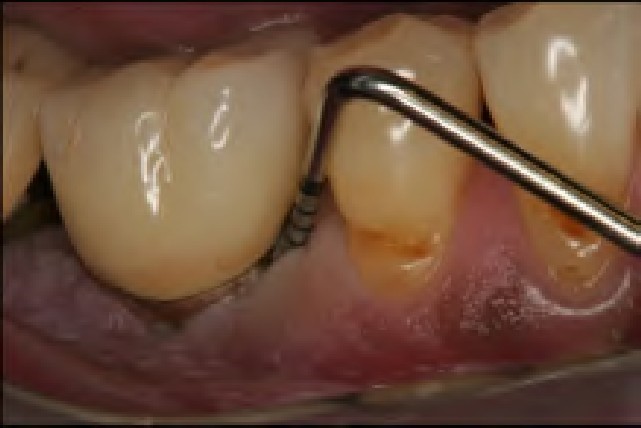

Early and accurate diagnosis of peri-implant diseases is predicated on specific reliable diagnostic indicators (eg, bleeding on probing, suppuration).30,31 The absence of bleeding on probing around implants indicates healthy peri-implant tissue, although debate continues regarding whether probing dental implants is prudent.30,32 However, when probing implants, a rounded, 25 Ncm probe is recommended. The soft-tissue seal inhibits probing depth penetration both in healthy and slightly inflamed peri-implant tissue, but not in peri-implantitis. Therefore, if bleeding on probing occurs and there are significant probing depths (eg, 5 mm to 8 mm), the site should be treated as early as possible.31,32

Because an implant can lose between 70% and 90% of bone—yet still not be mobile—mobility is not a good diagnostic indicator of peri-implantitis.33 Additionally, because radiographs may produce too many false negatives, and based on their low sensitivity for detecting early changes, they are not reliable diagnostic indicators of peri-implantitis.33 Therefore, viewing radiographs over time to observe the bone level and any changes is advisable to determine when and if disease is present and treatment should be initiated.31,33